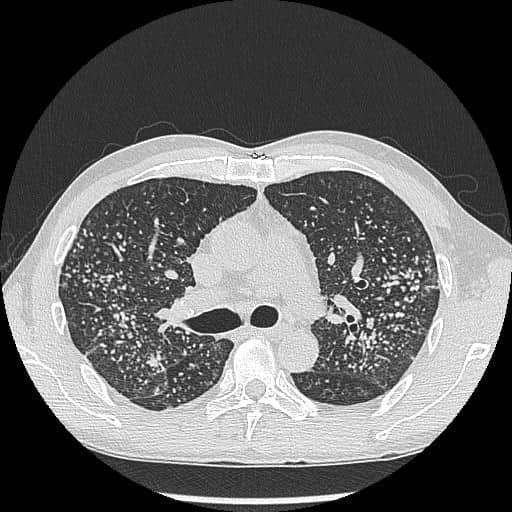

疫苗研發於目前取得了重大進展,第一批針對肺癌的疫苗「LungVax」已經誕生,並將在明年夏天啟動臨床試驗。這種疫苗採用與牛津-阿斯特捷利康新冠疫苗類似的技術,為免疫系統提供一組遺傳指令,透過細胞表面的一種稱為「腫瘤新生抗原(Neoantigens)」的「危險訊號」蛋白,識別可能導致肺癌的細胞,並與健康細胞作區分,讓免疫系統及早在異常細胞癌變前將其摧毀。